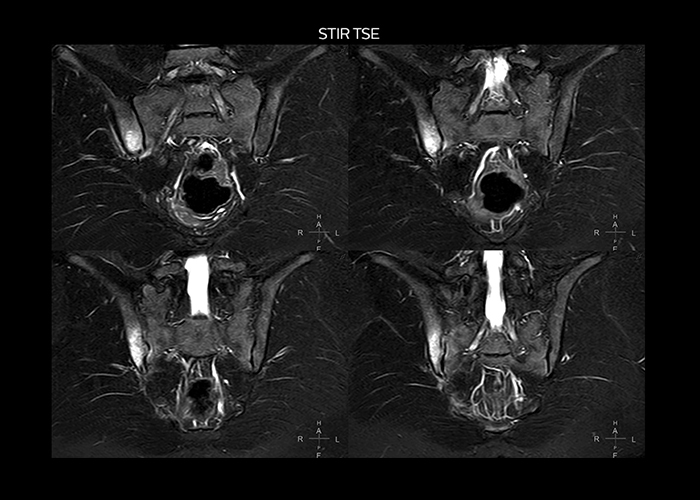

“To avoid coil changes we plan examinations of similar anatomies back to back, such as head and spine. Multiva helps us here a lot because coils don’t need to be changed frequently. Moreover, thanks to parallel imaging technology and 16-channel HeadSpineTorso and 8-channel MSK coils we are able to achieve excellent image quality. In this way Multiva helped us to increase both image quality and productivity.”

“Neurological cases, such as brain and spine imaging, represent the largest share in our MR scanning, followed by musculoskeletal cases. In general, we use simple and basic imaging protocols. But occasionally, we use advanced techniques for problematic cases if necessary.